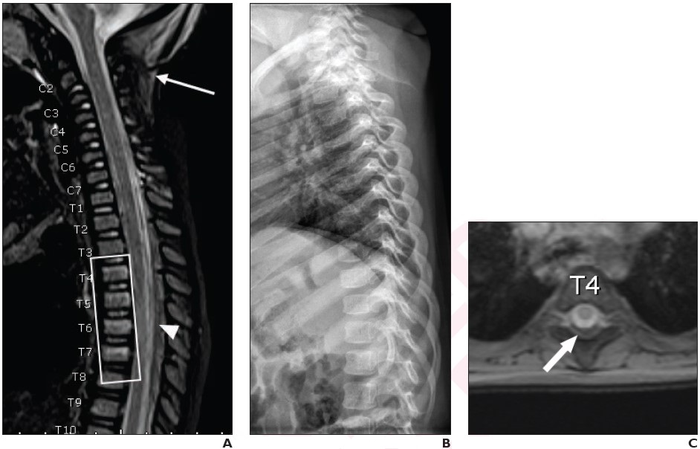

Leesburg, VA, January 12, 2022 According to an article in ARRS’ American Journal of Roentgenology ( AJR ) , whole-spine MRI commonly demonstrates isolated thoracolumbar injuries in children with suspected abusive head trauma.

“When performing spine MRI in children with suspected abusive head trauma, whole-spine MRI rather than cervical spine MRI may be warranted, to avoid missing isolated thoracolumbar injuries,” clarified first author Boaz Karmazyn from Indiana University School of Medicine, Riley Hospital for Children.

Of the 148 total children with suspected abusive head trauma who underwent whole-spine MRI, 23.0% of examinations demonstrated injuries localized to the thoracolumbar spine. Injuries were localized to the thoracolumbar spine in 51.1% of examinations with major findings: subdural hematoma, epidural hematoma, ligamentous injury, or fracture not identified by skeletal survey.